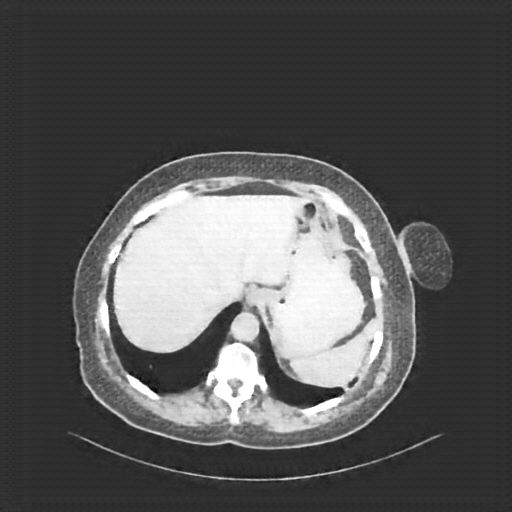

Reconstructed NATIVE CT scan (cycle consistency)

Full window (WL 1023.5, WW 4095 β†’ Low βˆ’1024, High +3071)

Actual HU range: [-1024.0, 690.2]